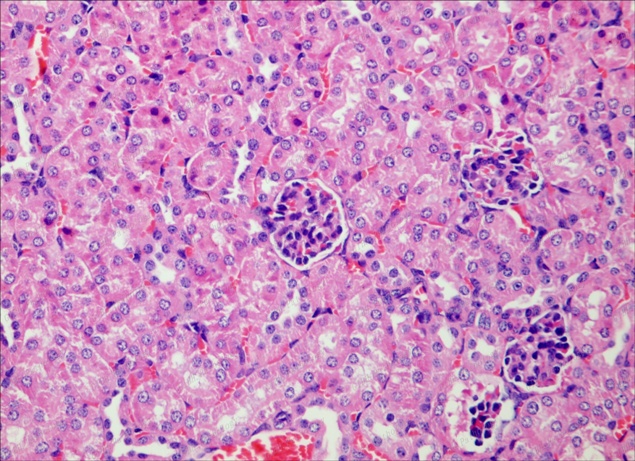

腎皮質40